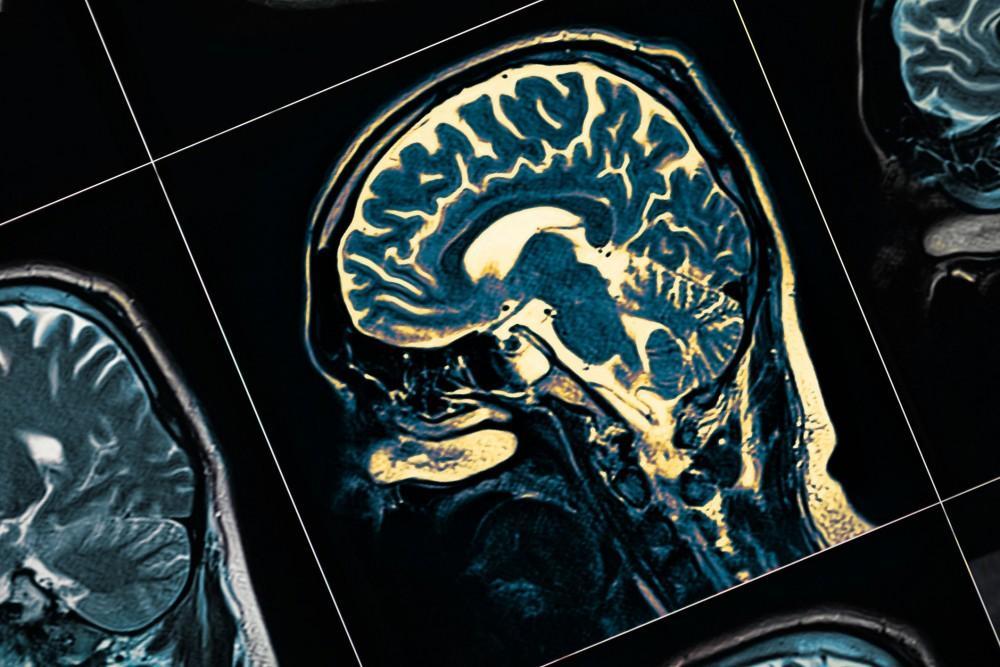

Evoked potential studies are performed to evaluate and measure the electrical activity that occurs in the brain in response to specific stimulation of the nerves responsible for sight, sound, and touch sensations. Although these tests are not designed to provide a confirmed diagnosis of a condition, they can be useful in providing additional information that can aid in diagnosis and in determining if additional testing is needed.

Although they usually don’t lead to a specific and definitive diagnosis, evoked potential studies can provide very important information about symptoms a person may be experiencing, helping to detect issues affecting vision, hearing, or the central nervous system. They’re often used to help confirm a diagnosis of multiple sclerosis, and they can also help identify issues affecting the optic nerve or central nervous system, including the detection of tumors.

Evoked potential studies are performed to evaluate and measure the electrical activity that occurs in the brain in response to specific stimulation of the nerves responsible for sight, sound, and touch sensations.

There are three types of evoked potential studies. These include visual evoked potential (VEP) tests, brainstem auditory evoked response (BAER) tests, and somatosensory evoked response (SSER) tests.

They’re often used to help confirm a diagnosis of multiple sclerosis, and they can also help identify issues affecting the optic nerve or central nervous system, including the detection of tumors.